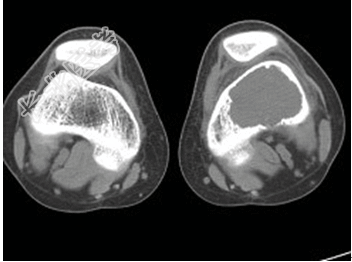

- [材料题] 患者,男,33岁,左股骨肿块半年余,无明显症状,查体一般情况良好。

- 简答题1、结合所提供的图像,该患者诊断为?